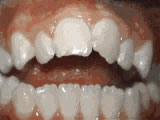

Phase-One Early Treatment

At age eight, patient had crowded lower teeth and displaced upper teeth; after 12 months of Phase-One treatment with an expander and partial braces, both appearance and dental function greatly improved.

Phase-One Early Treatment before Phase-One Early Treatment after